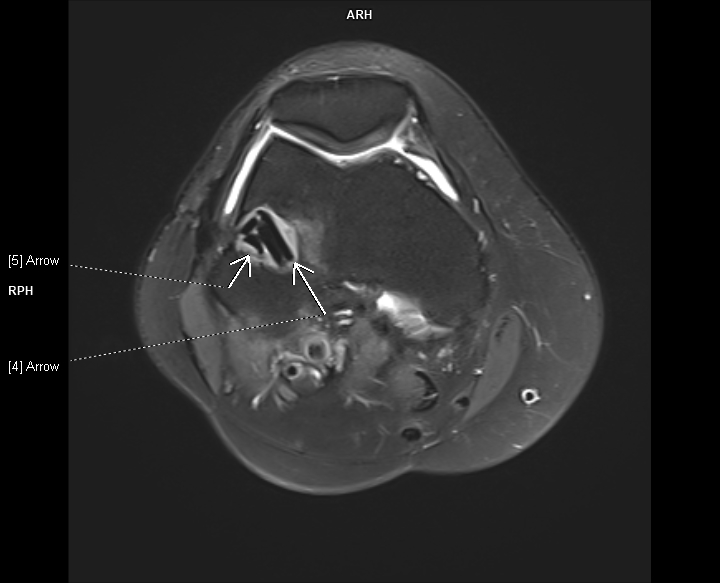

Figurile 1-3:  axial PD cu cu saturaţia grăsimii

Discuţie caz nr 107: la nivelul platoului tibial și posterior la nivelul condilului femural extern se evidențiază modificări de tip chistic în osul subcondral. În plus, a nivelul ligamentului colateral lateral se evidențiază o plajă limitată de lipsă de substanță în dreptul unei plaje de lipsă de substanță osoasă din condilul femural extern care este plombată postoperator.